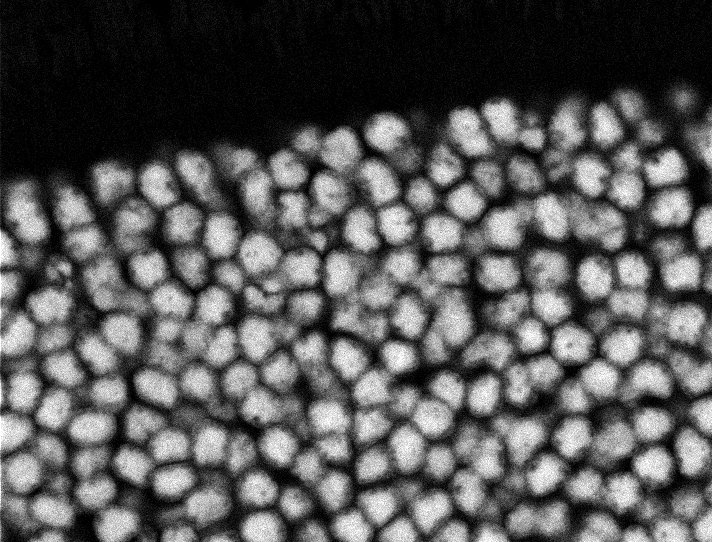

Nuclei - Bis

Nuclei